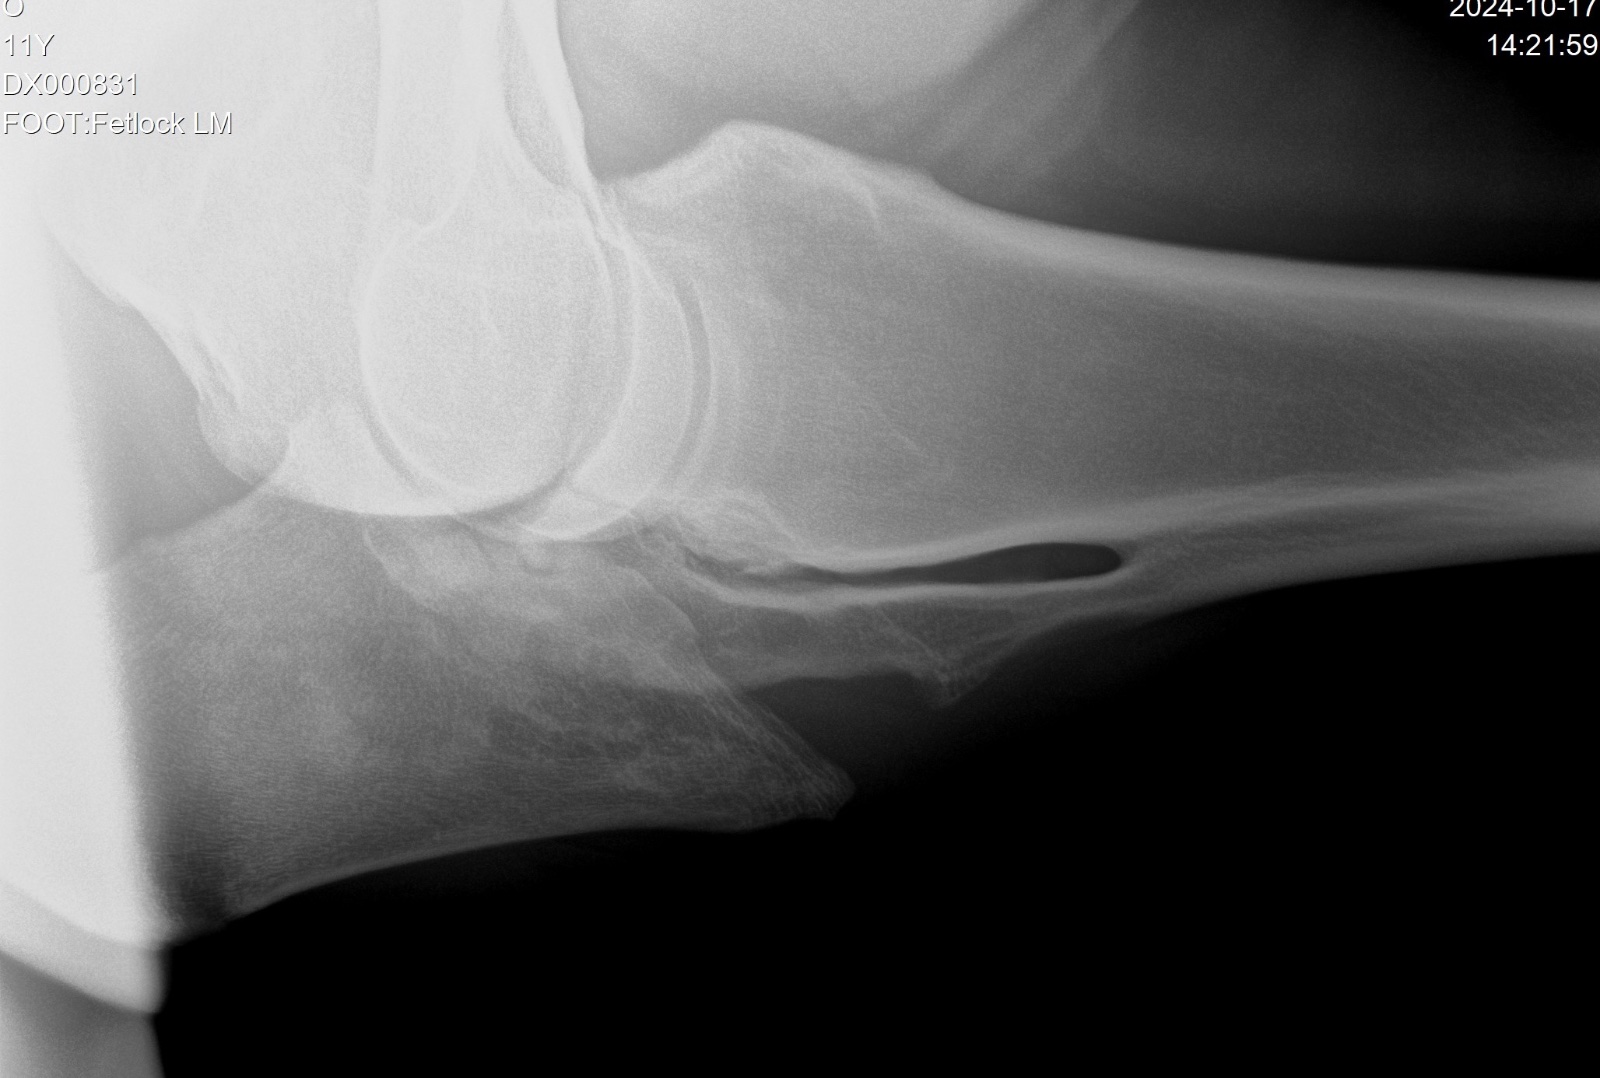

У нее классическое происхождение - Сандро Хит - Рубинштайн, выступала в спорте включительно по Средний приз, чистые рентгены. Я зарекалась, что больше никаких кобыл из спорта и вот опять - на колу мочало, начинай сначала